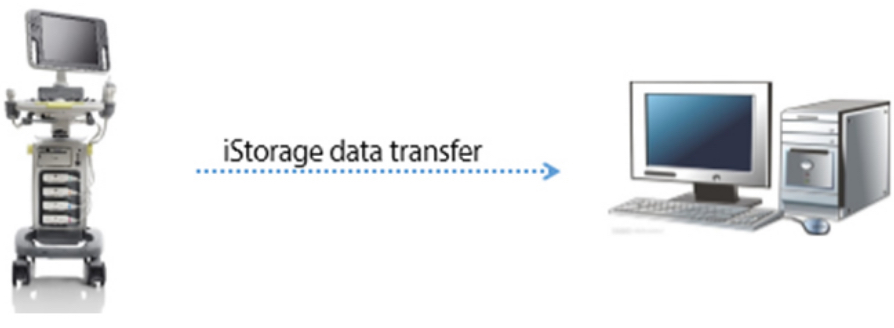

iStorage / iMeasurement / iReport

- iStorage: Mentransfer gambar dan laporan secara langsung ke PC lewat kabel jaringan.

- iMeasurement & iReport: Perangkat lunak PC offline untuk tabel pengukuran yang ditentukan pengguna, perhitungan rumus, dan template laporan.